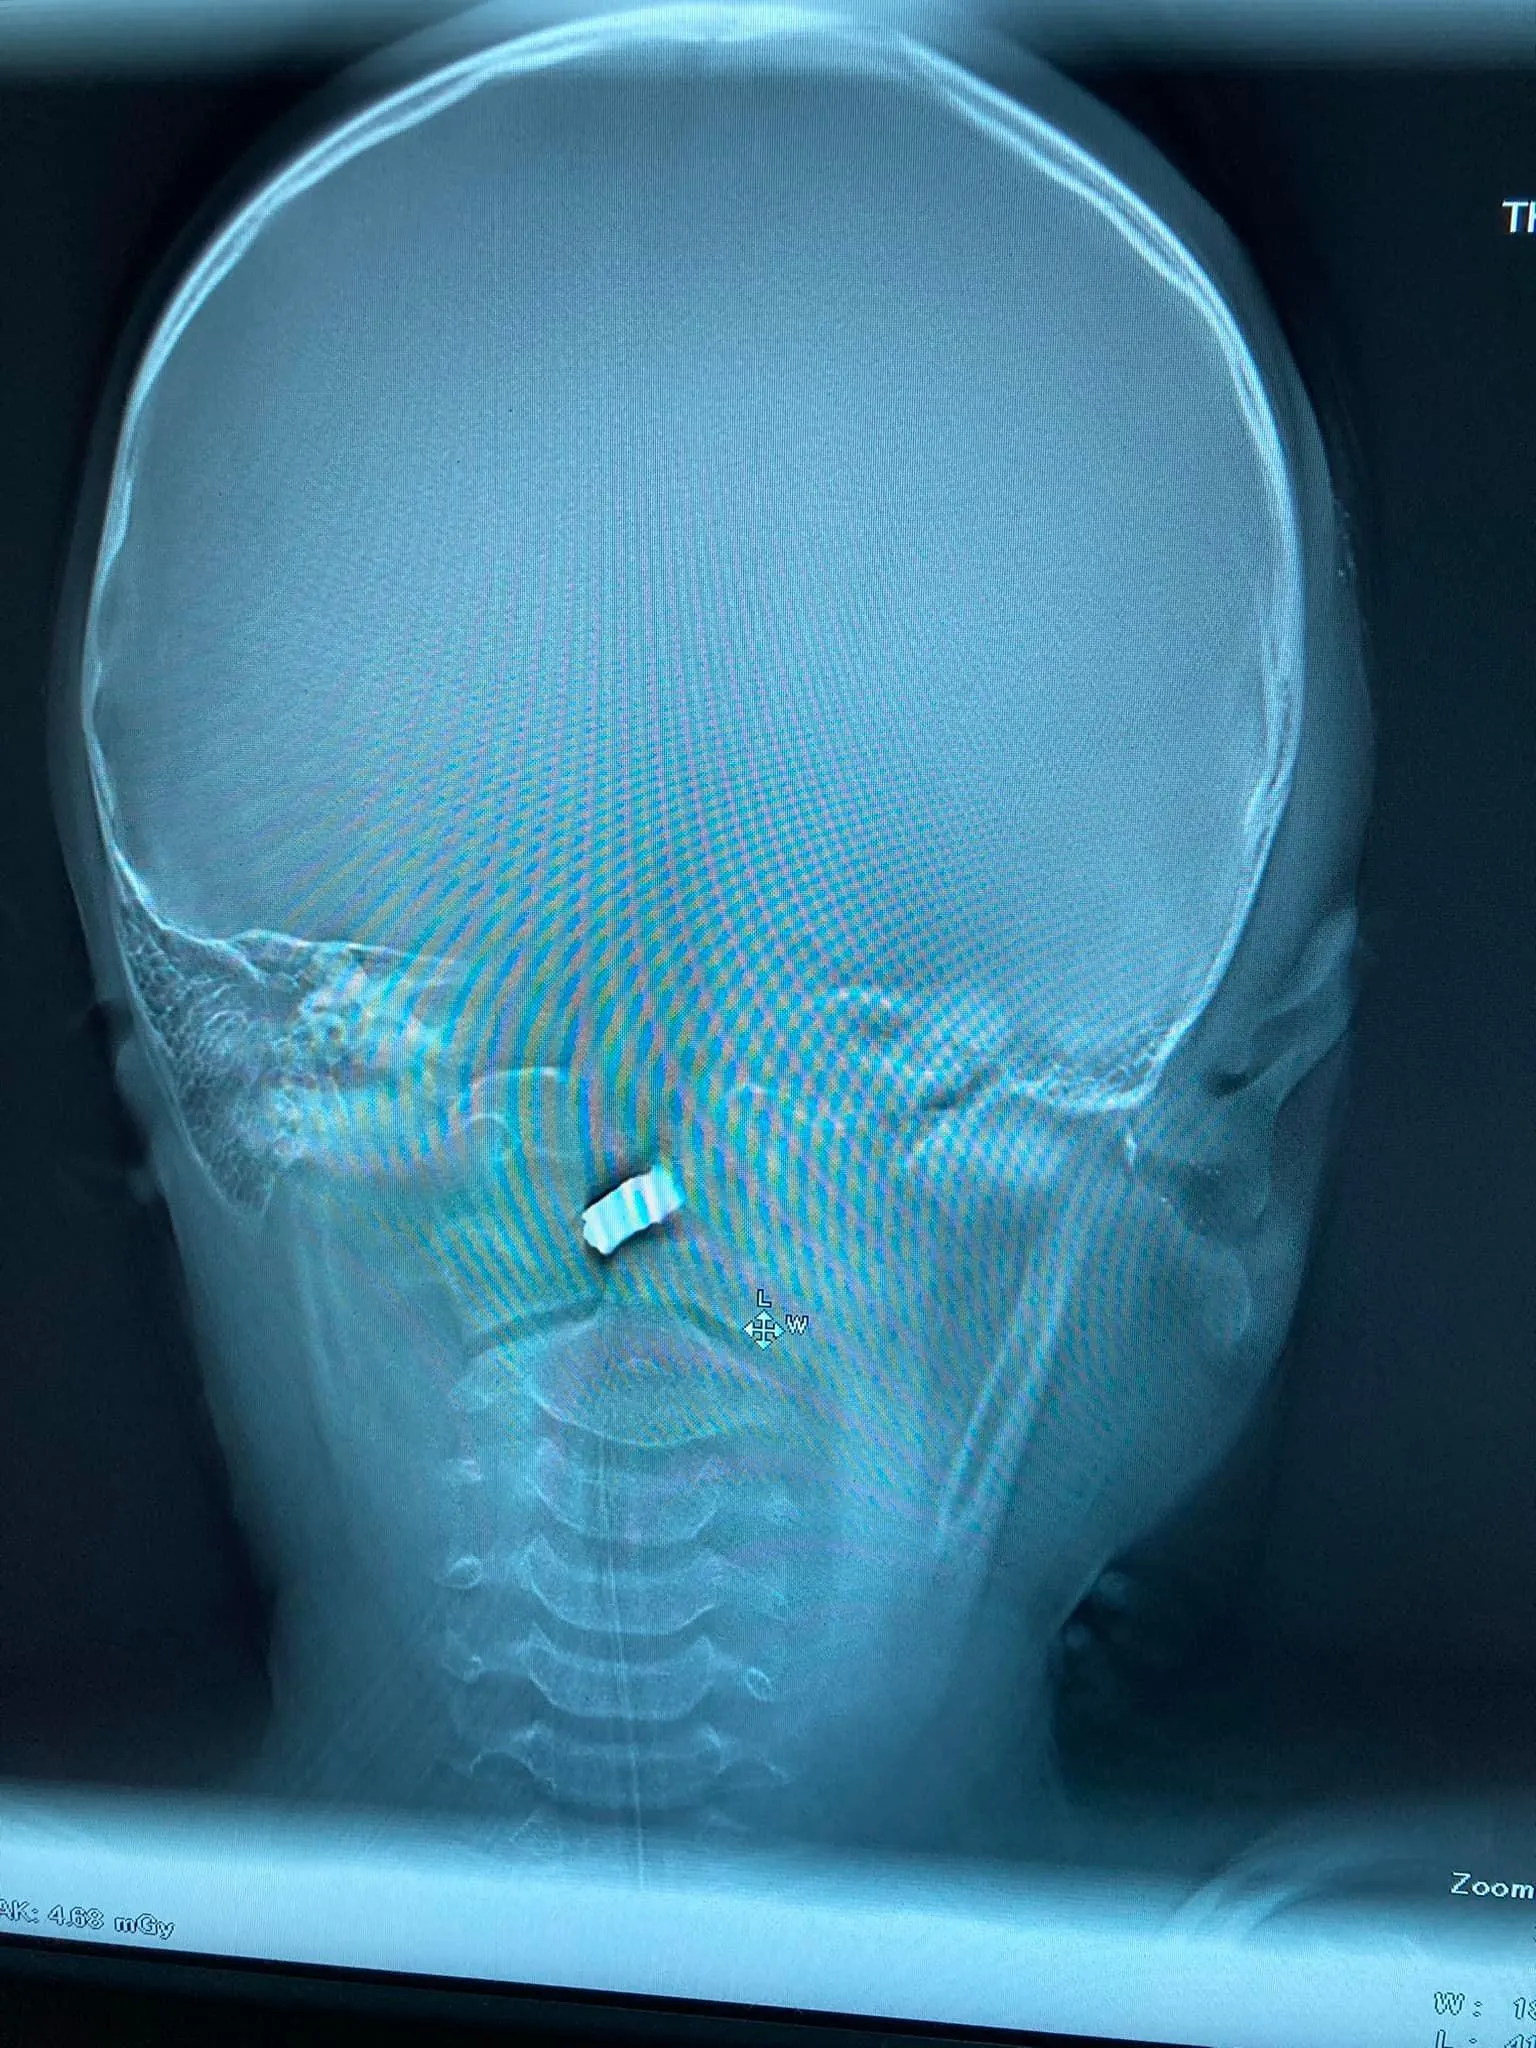

В комментариях к сообщению он добавил, что осколок вошел через скулу. Локализация – очень сложная, но ключевые артерии не задело.

Локализация сложная, но врачи работают / Фото Духновского